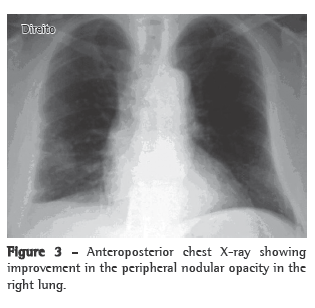

A 61-year-old male patient sought treatment at the pulmonology outpatient clinic reporting lung secretion with occasional bloody sputum for approximately 5 months. Within the past month, the patient had severe cough, dyspnea and a peak of fever. The patient reported no other respiratory problems and no history of occupational risk. He also reported long-term labyrinthitis and recent hypoacusis. He was a former smoker (30 pack-years) who had not smoked for 10 years. The physical examination revealed that the patient was well hydrated and with good color. He presented abnormal breath sounds, crackles in the right hemithorax base, increased vocal fremitus and a systemic arterial pressure of 120/80 mmHg. The SpO2 was 96%. The investigation began with imaging studies and laboratory tests. A chest X-ray showed a nodular opacity in the lower third of the right hemithorax (Figure 1a), a sinus X-ray revealed thickening of the left maxillary sinus mucosa, and a CT scan of the chest revealed an extensive lesion in the right hemithorax (4.2 cm × 3.1 cm), contiguous with the parietal pleura (Figure 1b). Based on these findings, we requested a tomography-guided percutaneous biopsy, which showed areas of fibrosis and areas of extensive necrosis associated with an inflammatory process (Figures 2a and 2b), whose possible causes include WG, bronchocentric granulomatosis or an infectious disease.

With treatment, the patient presented improvement of the clinical manifestations and the pulmonary alterations resolved (Figure 3).

Imaging studies showed an extensive unilateral nodular lesion. This finding is uncommon in WG and, therefore, there was diagnostic difficulty in view of the possibility of a malignant disease. What is expected in this type of vasculitis is pulmonary infiltration or bilateral multiple nodules, which can be accompanied by cavitations (in 50% of the cases).(8) The next step was then to resort to tomography-guided percutaneous biopsy, a procedure that has high sensitivity, specificity and accuracy, the last ranging from 84.5% to 90%, depending directly on the size of the lesion. The principal reason for requesting the procedure is to determine malignancy in solid pulmonary lesions.(9,10)